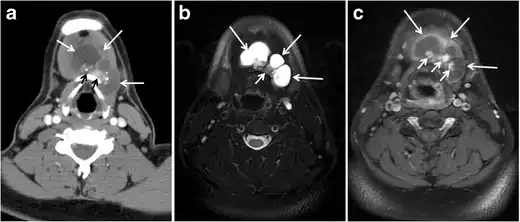

Fig. 11. Thyroid non-Hodgkin's large B-cell lymphoma in a 66-year-old female patient. an Axial enhanced neck CT scan demonstrates left thyroid lobe and isthmus homogeneously hypodense and minimally enhancing mass (white arrows). This lesion invades the prevertebral muscles (black arrows). Note the multiple enlarged level V lymph nodes (white arrowheads). b Post-treatment image shows significant reduction in size and mass effect of the left thyroid infiltrative mass, with almost complete resolution of the left cervical lymphadenopathy.[1] -